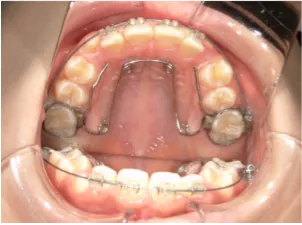

治療中③中1:非抜歯治療の診断で、上顎に歯の生えるスペースをつくるため上顎左右6をプレートで遠心移動し、隙間ができた時点

| 行ったご提案・診断内容 | 生え変わりが終わってなくマルチブラケット法による咬合治療には早い時期のため、顔立ちの成長を促す目的で歯列弓(アーチ)の拡大と前歯を並べながら永久歯が生えるのを待ち、咬合治療開始時に再診断で抜歯、非抜歯を最終検討する提案をしました。 再診断時(写真②)、歯列の拡大と上顎前歯の並べ替えはされていましたが八重歯となったため抜歯、非抜歯を検討しました。 口元は特に問題がなく非抜歯で八重歯を改善するためのスペースを作ることが可能なため非抜歯治療を提案しました。 治療は、 ・拡大および上顎左右6を遠心移動させてスペースを作る 予定装置 |